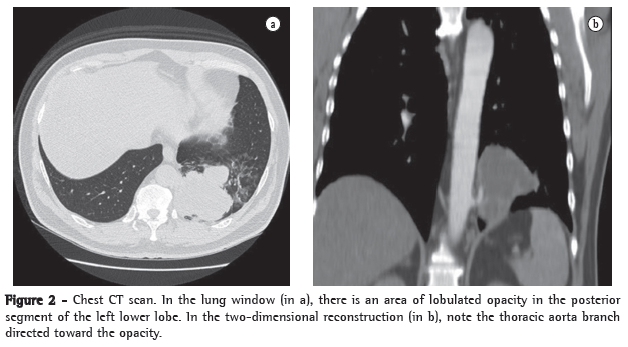

Physical examination revealed good general health, no fever, an HR of 88 bpm and an arterial pressure of 90-145 mmHg. The cardiac auscultation was normal, and examination of the lung revealed reduced expansion and diminished breath sounds in the lower third of the left hemithorax, as well as dullness to percussion in this same region. The rest of the physical examination revealed no abnormalities. The results of the laboratory tests performed at admission, such as blood workup, lipid profile, coagulation profile, determination of electrolyte concentrations, renal function test and hepatic function test, were normal. The ESR was 32 mm/h. Serology for HIV was negative. A chest X-ray at admission revealed opacity in the posterior segment of the left lower lobe (Figure 1). A CT scan of the chest with two-dimensional reconstruction revealed an aortic branch directed toward the pulmonary opacity (Figure 2), which is consistent with a diagnosis of pulmonary sequestration. The patient was referred for surgery, and a left lower lobectomy was performed to resect the anomalous pulmonary tissue (Figure 3). After the macroscopic analysis of the surgical sample, the patient was diagnosed with intralobar sequestration. The postoperative evolution was favorable, and the patient was discharged to outpatient treatment.

When faced with a 56-year-old patient, admitted for investigation of hemoptysis, with no clinical evidence of respiratory infection, with no history of smoking and having an area of opacity in the posterior segment of the left lower lobe on chest X-ray, one of the hypotheses to be considered is that it is a case of pulmonary sequestration.